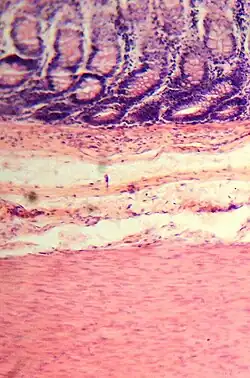

Colonic crypts

The wall of the large intestine is lined with simple columnar epithelium with invaginations. The invaginations are called the intestinal glands or colonic crypts.

The colon crypts are shaped like microscopic thick walled test tubes with a central hole down the length of the tube (the crypt lumen). Four tissue sections are shown here, two cut across the long axes of the crypts and two cut parallel to the long axes. In these images the cells have been stained by immunohistochemistry to show a brown-orange color if the cells produce a mitochondrial protein called cytochrome c oxidase subunit I (CCOI). The nuclei of the cells (located at the outer edges of the cells lining the walls of the crypts) are stained blue-gray with haematoxylin. As seen in panels C and D, crypts are about 75 to about 110 cells long. Baker et al.[30] found that the average crypt circumference is 23 cells. Thus, by the images shown here, there are an average of about 1,725 to 2,530 cells per colonic crypt. Nooteboom et al.[31] measuring the number of cells in a small number of crypts reported a range of 1,500 to 4,900 cells per colonic crypt. Cells are produced at the crypt base and migrate upward along the crypt axis before being shed into the colonic lumen days later.[30] There are 5 to 6 stem cells at the bases of the crypts.[30]

As estimated from the image in panel A, there are about 100 colonic crypts per square millimeter of the colonic epithelium.[32] Since the average length of the human colon is 160.5 cm[11] and the average inner circumference of the colon is 6.2 cm,[32] the inner surface epithelial area of the human colon has an average area of about 995 cm2, which includes 9,950,000 (close to 10 million) crypts.

In the four tissue sections shown here, many of the intestinal glands have cells with a mitochondrial DNA mutation in the CCOI gene and appear mostly white, with their main color being the blue-gray staining of the nuclei. As seen in panel B, a portion of the stem cells of three crypts appear to have a mutation in CCOI, so that 40% to 50% of the cells arising from those stem cells form a white segment in the cross cut area.

Overall, the percent of crypts deficient for CCOI is less than 1% before age 40, but then increases linearly with age.[29] Colonic crypts deficient for CCOI in women reaches, on average, 18% in women and 23% in men by 80–84 years of age.[29]

Crypts of the colon can reproduce by fission, as seen in panel C, where a crypt is fissioning to form two crypts, and in panel B where at least one crypt appears to be fissioning. Most crypts deficient in CCOI are in clusters of crypts (clones of crypts) with two or more CCOI-deficient crypts adjacent to each other (see panel D).[29]